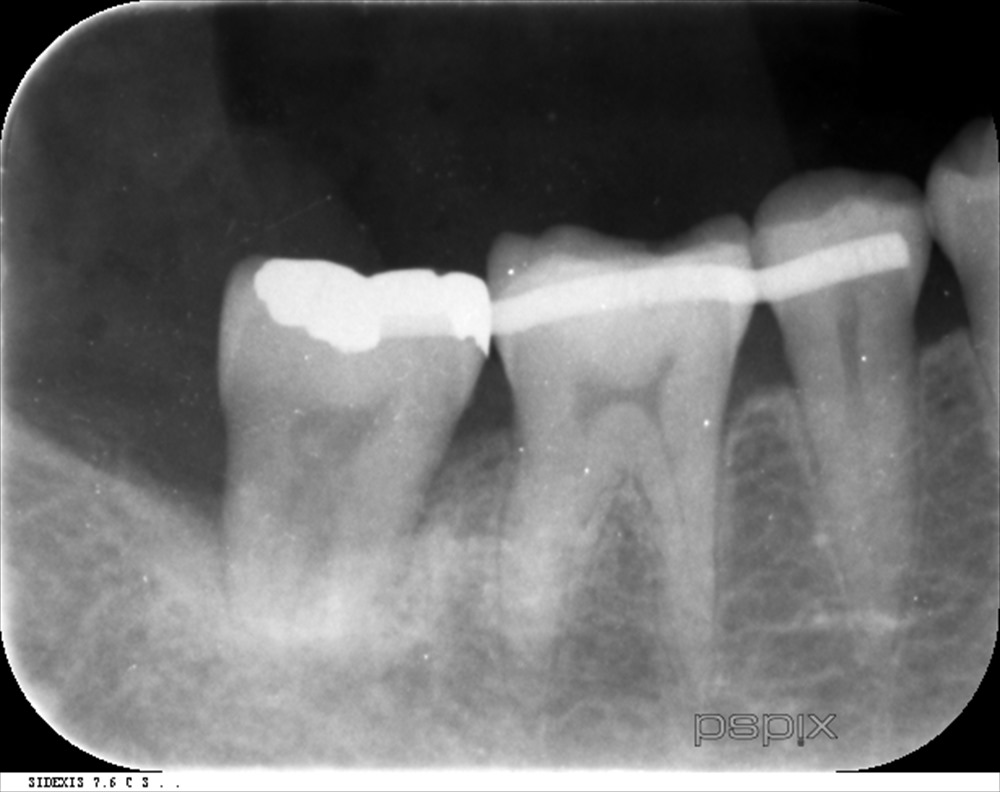

約4ヶ月

歯肉は安定し、骨様組織が出来ている様に見えます。この症例は一切、再生材料などを使用していません。

「血餅の安定しやすい状態」

を作っただけです。